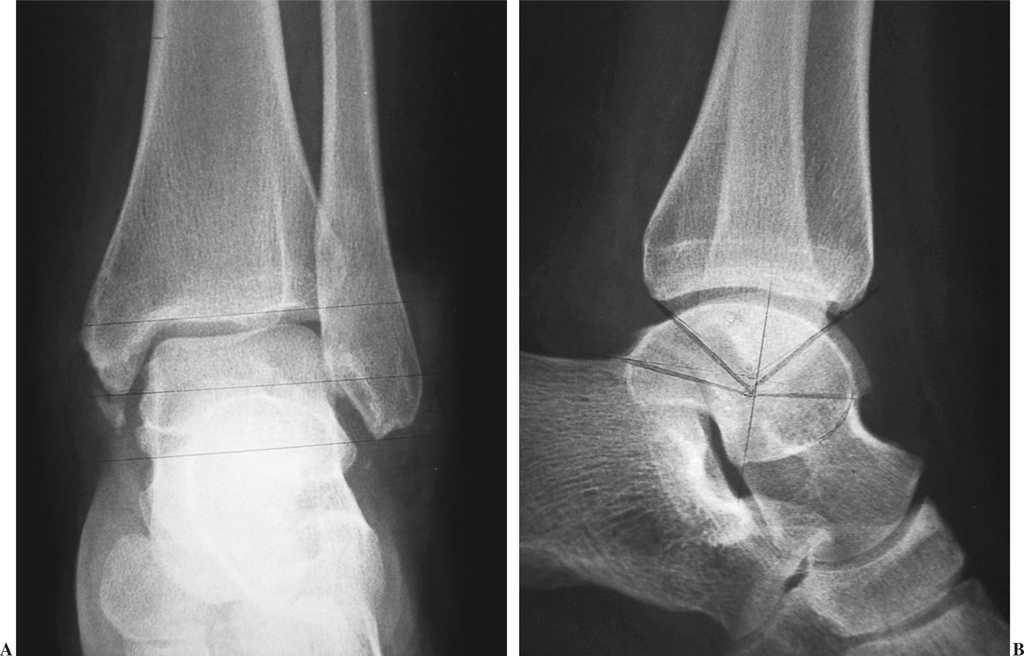

From revistamedica.com

Estudio radiológico del tobillo Ocronos Editorial CientíficoTécnica Como Se Ve Un Tobillo Dislocado ¿cómo se diagnostica la dislocación del tobillo? Una dislocación es una lesión que hace que los huesos de una articulación se salgan de posición. Un tobillo dislocado ocurre cuando uno o más de los huesos que forman la articulación del tobillo (peroné, tibia y astrágalo) se mueven de su. La causa suele ser una caída o un golpe y, algunas. Como Se Ve Un Tobillo Dislocado.